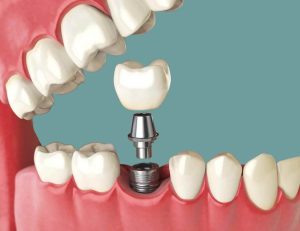

ایمپلنت فوری یا Immediate Implant به روشی گفته میشود که در آن پایه ایمپلنت بلافاصله پس از کشیدن دندان در همان جلسه در استخوان فک قرار داده میشود و در برخی موارد، روکش موقت نیز همان روز روی آن نصب میگردد.

مرحله سوم: کاشت پایه ایمپلنت

مرحله ششم: نصب روکش دائمی

پس از اطمینان از ثبات کامل، روکش نهایی سرامیکی یا زیرکونیا نصب میشود.